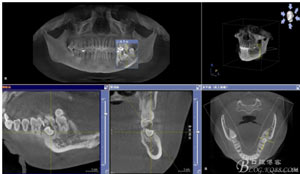

患者、申xx、女、40歲,主訴:左側(cè)下頜后牙牙齦紅腫不適數(shù)月。??茩z查:37合面有一開(kāi)髓孔。髓腔內(nèi)有一暫封小棉球,探針?biāo)枨坏撞砍鲅蔀樵谕庠褐委煂?dǎo)致底穿。x線片檢查:37頰側(cè)齦下有一枚多生牙,多生牙壓迫頰側(cè)牙根及牙體組織大量吸收。

圖1.術(shù)前的CBCT檢查:37頰側(cè)部分牙根被完全壓迫吸收。